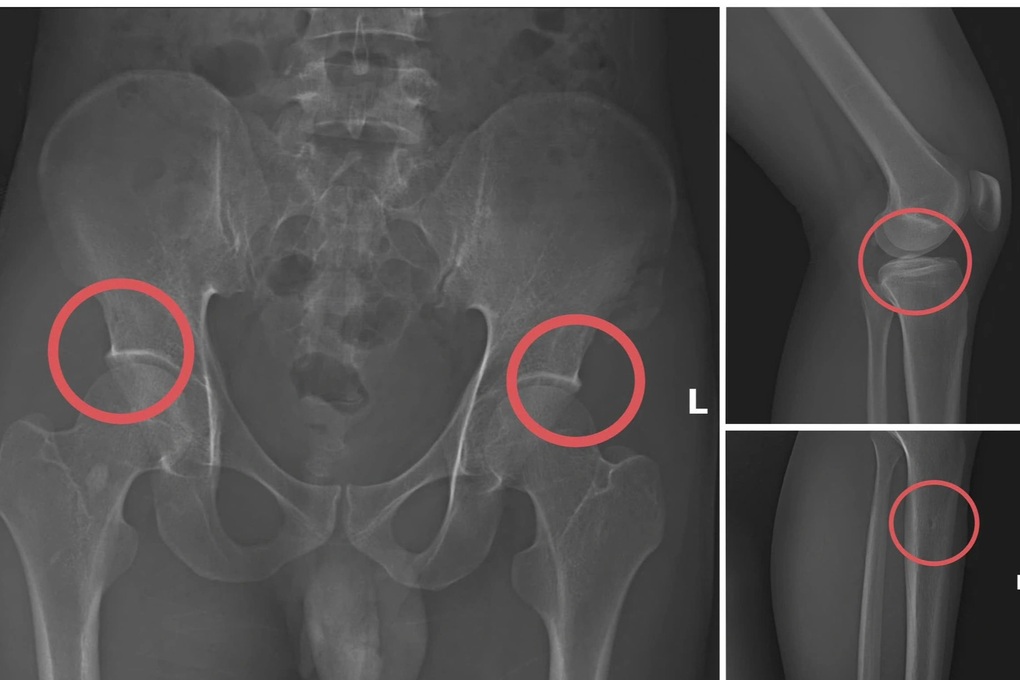

Châu trực tiếp thực hiện hành vi tiêm thuốc mê rồi dùng kim tiêm, búa, đinh để tác động vào xương người mua bảo hiểm, tạo nên các vết nứt, vỡ xương tương tự tai nạn thật.

Một số tổn thương xương do các đối tượng tạo ra nhằm trục lợi bảo hiểm nhân thọ (Ảnh phim chụp XQ, Công an tỉnh Phú Thọ cung cấp).